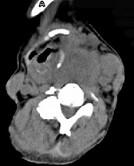

问题 女,64岁,双甲状腺占位40余天。如图所示甲状腺病灶应诊断为()

选项 A.结节性甲状腺肿 B.甲状腺腺瘤 C.甲状腺癌并淋巴结转移 D.甲状腺转移瘤 E.甲状腺结核

答案 C